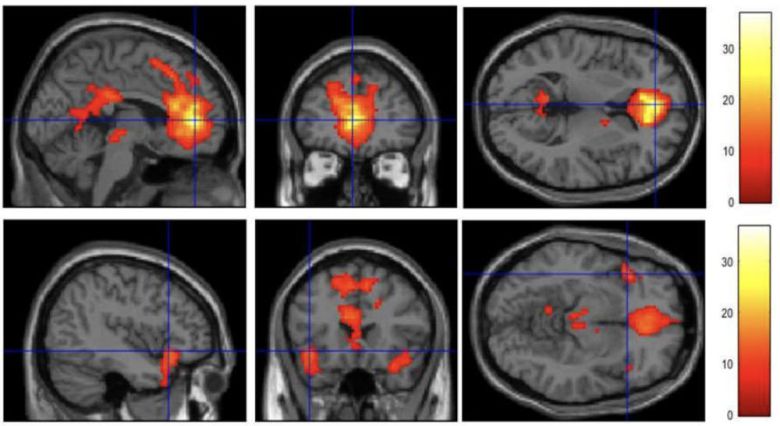

10일 문화체육관광부에 따르면 올해 11월까지 1억원을 들여 게임이용자 임상의학 코호트 연구를 진행한다. 게임 이용자 변화를 장기적으로 파악하는 종단 데이터를 확보하는 것이 목표다. 휴지기상태 기능적 자기공명영상(rs-fMRI) 뇌 영상 데이터를 활용해 기능적 연결성을 분석한다. 문체부는 게임이용장애, 게임과몰입 등 현안에 대응하는 정책적 기초자료로 활용할 계획이다.

실제 1·2차년도 뇌과학 임상 코호트 연구를 통해 게임과몰입 주요영향이 게임 자체 문제가 아니라 공존질환, 심리상태 영향 요인이 있음을 규명했다. 주의력결핍과잉행동장애(ADHD)점수와 사회불안 점수는 음의 상관관계를 가지며 게임선용군이 과도한 게임 행동을 스스로 멈추고 조절할 수 있다는 뇌과학적 증거를 발견했다. 중독 기전보다는 ADHD 기전과 유사하다는 관련성을 찾아내 사회과학 패널 연구 결과를 뒷받침하는 성과를 거뒀다.